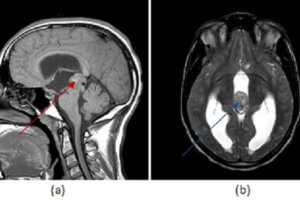

Chiari malformation Type 1

Chiari Malformation

Arnold Chiari 1 malformation is a congenital anomaly of the brain parenchyma characterized by descent of the cerebellar tonsils below the foramen magnum due to a mismatch between the size of the... Read more »